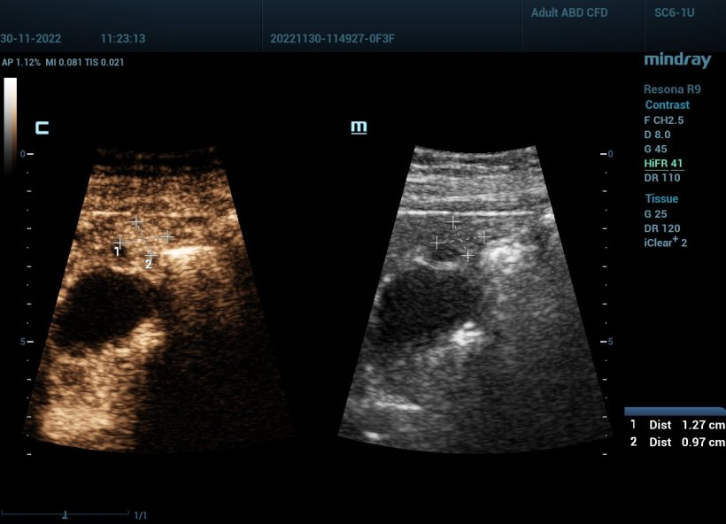

?? 6? ?? ??? ??? ????? HiFR CEUS(????? ?? ?? ???)? ??? ??? ???? ??? ????? ?? ?? ? ??? ? ???? ??? ? ???? ?????.

Yi Dong: '?? ??? ???? ??? ???? ?? 3cm ??? ?? ? ??? ?? ???? ???? ????. ?? ????? HiFR CEUS? ??? ??? ??? ?? ??? ???? ????? ??? ??????. HiFR CEUS? ??? ??? ???, ? ?? ?? ? ??? ??? ??? ??? ??? ?????. ?? ?? ??? ??? ??? ? ??? ?? ???? ?? ????. HCC(??? ??)? ?? ?? ????? ?? ??? ???? ????? ?? ??? ? ??? ?????? ?? ??? ??? ??? ??????.'

Christoph Dietrich: '???? ??? HCC ?? ??? ????. ???? ???? 30mm?? ? ??? HCC? ???? ????. ?? ??? 12mm? ???? HCC? ???? 50%? ?????. ????? ?? ??? ???? HCC? ???? ??? ?? ?? ??? ??? ??? ???? ??? ?? ??? ???? ? ??? ????? ? ?????. ???? ?? HCC? ??? ??? ? ??? ?? ? ??? ????? ??? ???? ????. ??? ??? ?? ?? ?? ?????? ??? ???? ??? ?? ??? ?? ????.'

Yi Dong: 'HiFR CEUS? ?? ???, ??? ? ???? ???? ?? ? ?? ???? ?? CEUS? ??? ??? ?????. ???? ??? ? ?? ?? ??? ?? ?????. ??? ??? HiFR CEUS? ??? CEUS?? ????? ?? ???? ?? ??? ? ?? ???, ? ? ?? ??? ??? ????? ???.'

Yi Dong: '??? ??? ????? ??? ?? ?? ??? ??? ??? ?? ? 10??????. ??? ???? HiFR CEUS ???? Mindray Resona 9? ?? ? ????. ?? ?? 100?? ??? ??? ? ????. ??? ?? ????? ?? ??? ? ? ????? ?? ?? ?? ?? ??? ??? ??? ? ? ?????. ??? ???, CEUS? ?? ???? ??????. ???? ??? ?? CEUS ??, ?? ?? ?? ??, ?? ?? ??, ?? ? ?? ?? ?? ?? ??? ??? ?? ????.'